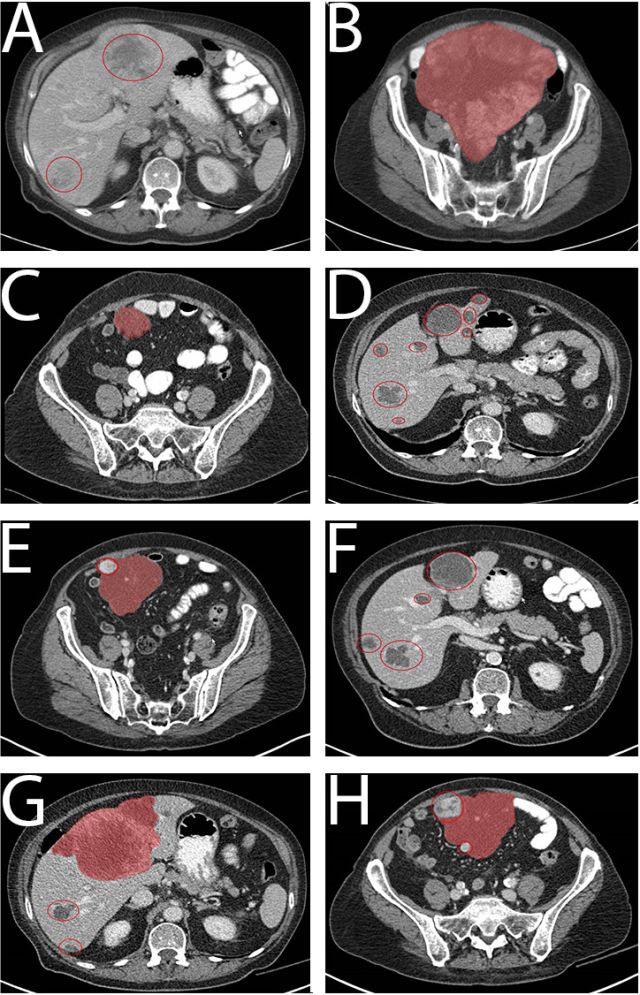

一例74岁患有原发性十二指肠间质瘤(GIST)的女性患者因心源性休克收入我院急诊科,死于心外肿瘤破裂导致的心脏骤停。冠状动脉CT血管造影(图A)显示肿瘤有来自右冠状动脉和左前降支的营养血管。血汗管磁共振(图B)显示肿瘤(箭头)具有不均匀强化,起自心肌。患者选择接受保守治疗。尸检于心室浆膜下检测到一个7×8×7厘米的弹性软肿瘤。病理示呈纤维样增生的轻度非典型梭形细胞(图C),CD117(c-kit)阳性(图D)。因此,该心外肿瘤被诊断为GIST转移。虽然三分之二的GIST转移患者为肝转移,心脏转移较罕见。